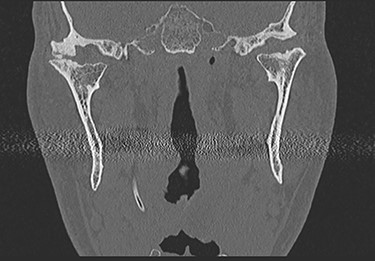

This report is about a 63-year-old patient suffering of bilateral deforming TMJ arthrosis (Wilkes-V) from a bilateral condylar fracture. In 2019 he presented himself to the Department of Oral and Maxillofacial Surgery, showing painful palpation above both TMJs and a severely decreased mouth opening (maximum interincisal distance of 1.5 cm). A computed tomography (CT) scan then revealed pathognomonic changes with flattening of the condyle and articular eminentia as well as partial ankylosis of the right TMJ (Fig. 1). Based on these findings, we decided for a bilateral TMJ-TJR. At this point, the patient only wanted one side replaced for the time being. After impressions were taken, plaster models were 3D-surface scanned and in combination with the CT dataset further processed by Zimmer-BiometTM (Warsaw, USA) for patient-specific TJR (PSI-TJR) fabrication. Another 3 months later, the TMJ-TJR of the right side could be carried out (Fig. 2). Postoperatively the patient received antibiotics for overall 7 days. Satisfied with the result, the patient requested reconstruction of the left TMJ 6 months later. With an improved mouth opening (2.8 cm), impressions were taken using an intraoral scanner. After PSI fabrication, the operation was carried out 9 months after (Fig. 3). Six weeks following surgery, the patient presented with a painful preauricular swelling on the left side, which was diagnosed as aseptic inflammation in the absence of erythema and pathologic joint puncture. Showing a periarticular edema, a broken screw and radial osteolysis around the drilling channels, a subsequent CT scan indicated the loosening of the ultra-high-molecular-weight-polyethylene (UHMWPE) fossa component (Fig. 4). In view of the long production time of new custom-made components and the damaged implant site, we decided to explant the fossa and to temporarily replace it with a non-fixed patient-specific spacer made of COPAL®-bone-cement (Fig. 5) (gentamicin and clindamycin additive) (Haereus; Hanau, Germany). The workflow included the surface scan of the original fossa-drilling template, the computer-aided design of a two-part press mould and the intraoperative fossa fabrication from COPAL®-bone-cement. With the use of a rubber elastic intermaxillary fixation, the vertical mandibular relation could be secured, painful movements and muscle shortening avoided and the risk of perioperative infection could be sufficiently minimized (Fig. 6). After 3 months without complications, the patient-specific COPAL® component could be removed and the new patient-specific UHMWPE fossa inserted within sufficiently regenerated bone (Fig. 7).

CT in coronal view with pathognomonic picture of deforming temporomandibular joint arthrosis on both sides.